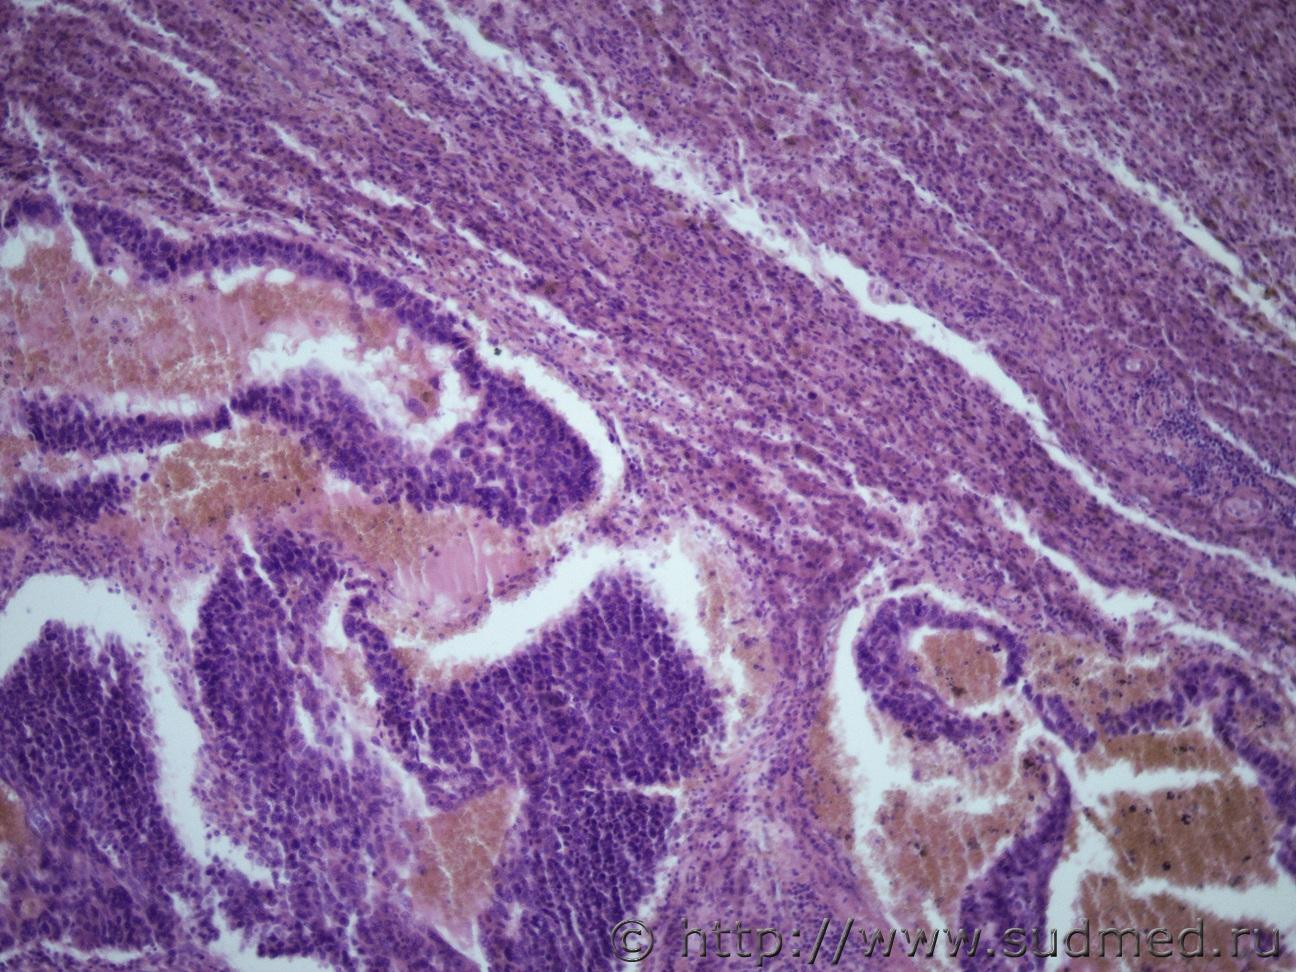

Ув. коллеги. Как и всегда необходима ваша профессиональная помощь. Жен 67 лет. На вскрытии - структура поджелудочной железы нарушена, гнойное распловление тела и хвоста пж, в области головки пж определяется плотноватый узел диаметром 5.5 см, богато васкуляризированный, на разрезе молочно-белого цвета с желтоватым оттенком, по консистенции близок к творожной массе. В области правой доли печени аналогичный узел. Судебная медицина - Прикрепленное изображение Судебная медицина - Прикрепленное изображениеСудебная медицина - Прикрепленное изображениеСудебная медицина - Прикрепленное изображениеСудебная медицина - Прикрепленное изображение

Метастатическая карциноидная ( нейроэндокринная)опухоль ( круглоклеточная монморфность с гиперхромными ядрами и некроз)

карциноидная ( нейроэндокринная)опухоль

Поддерживаю.